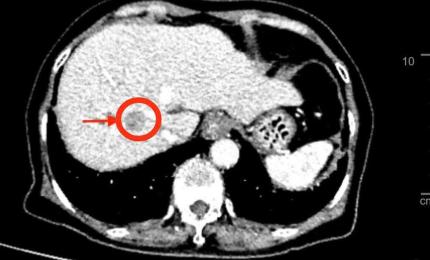

Tình cờ phát hiện ung thư phổi nhờ khám sức khỏe định kỳ

'Tôi chưa bao giờ nghĩ rằng ở tuổi 29, không hút thuốc, sinh hoạt điều độ và hoàn toàn khỏe mạnh lại có thể mắc ung t